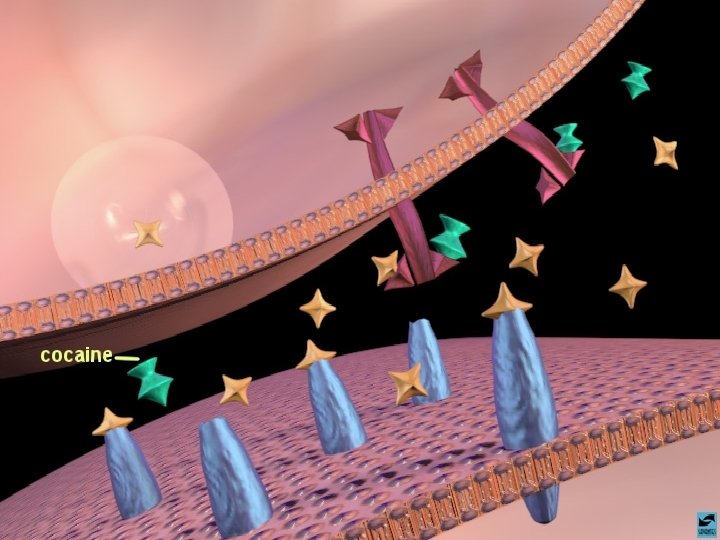

ANFETAMINAS E COCAÍNA EFEITOS CEREBRAIS: ATIVA OS SISTEMAS DOPAMINÉRGOS MESOLÍMBICOS E MESOCORTICAIS, INIBINDO A RECAPTAÇÃO DE DOPAMINA NOS TERMINAIS SINÁPTICOS E PROMOVENDO SUA LIBERAÇÃO NAS SINAPSES.